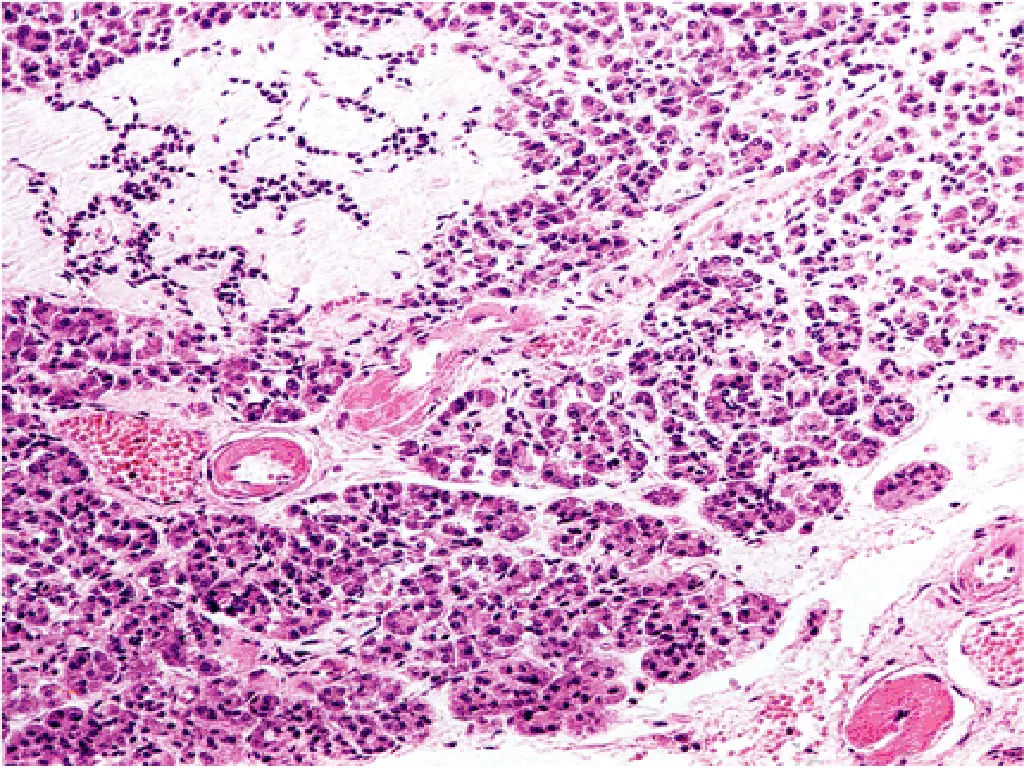

2- AUTOIMMUNITY: Patients who die shortly after the onset of the disease often exhibit an infiltrate of mononuclear cells in and around the islets of Langerhans, termed insulitis

Cell-mediated immune mechanisms are fundamental to the pathogenesis of T1DM ,CD8+T lymphocytes pre- dominate, although some CD4+cells are also present. The infiltrating inflammatory cells also elaborate cytokines, for example, IL-1, IL-6, interferon-alpha, and nitric oxide, which may further contribute to B cell injury. An autoimmune origin for T1DM was initially suggested by the demonstration of circulating antibodies against components of the B cells (including insulin itself) in most newly diagnosed children with diabetes.

Lymphocytic infiltrate in the islets (insulitis), sometimes accompanied by a few macrophages and neutrophils As the disease becomes chronic, the B cells of the islets are progressively depleted of Beta cells Fibrosis of the islets is uncommon. In contrast to T2DM, deposition of amyloid in the islets of Langerhans is absent in T1DM. The exocrine pancreas in chronic T1DM often exhibits diffuse interlobular and interacinar fibrosis, accompanied by atrophy of the acinar cells.